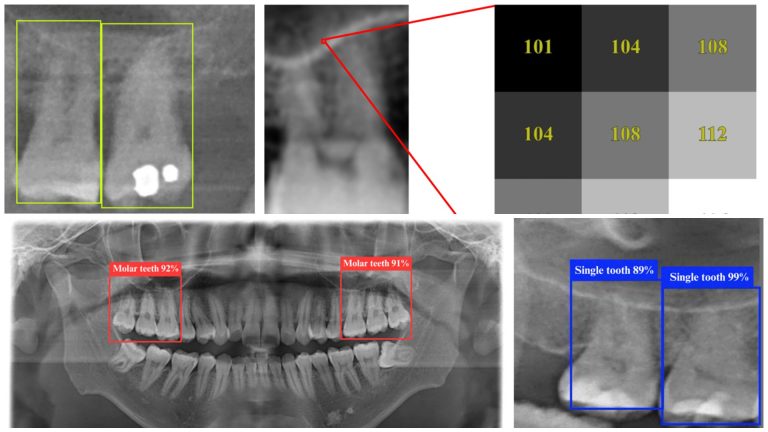

Using the YOLO 11n deep learning model, researchers trained AI to analyze dental panoramic radiographs (DPRs) with unprecedented precision. YOLO (You Only Look Once) is a high-speed object detection algorithm optimized for medical imaging. The model can pinpoint key anatomical relationships, such as the proximity of tooth roots to sinuses, in real time. Unlike conventional diagnostic methods that require multiple steps, YOLO 11n accelerates the detection process, making it a valuable tool for dental professionals.